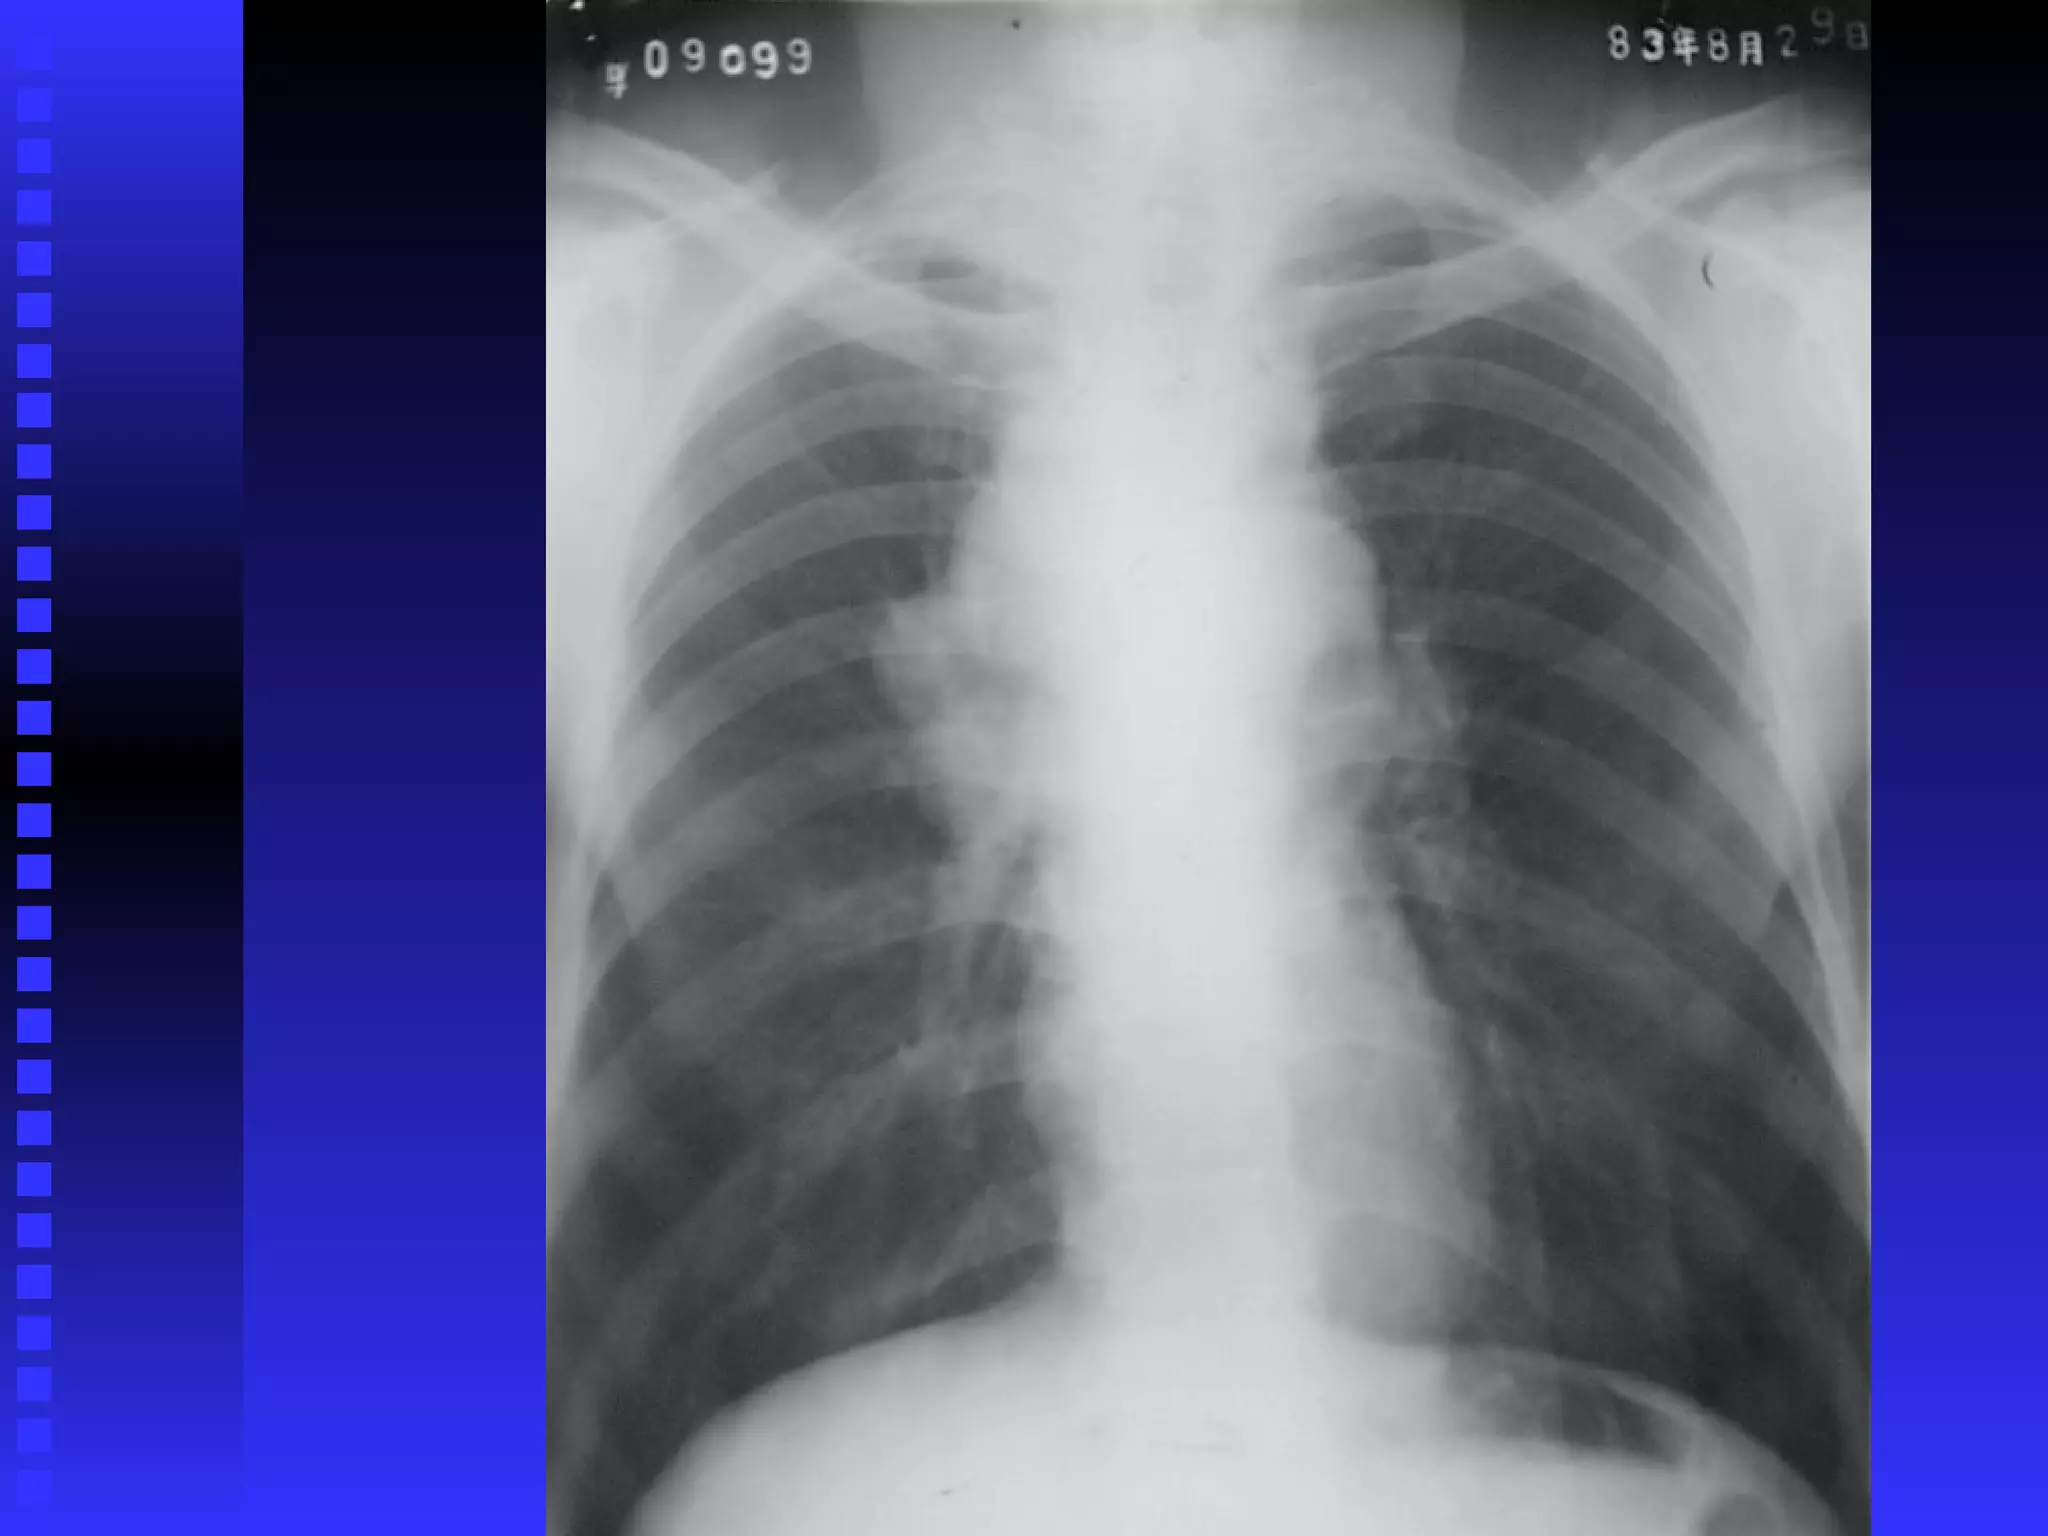

ETAPIFICACIONETAPIFICACION

1.1. Clínica y Patoló gicaClínica y Patoló gica

2.2. Examen físicoExamen físico

3.3. Biopsia de ganglioBiopsia de ganglio

4.4. Radiología, Rx Torax, TAC, RMNRadiología, Rx Torax, TAC, RMN

5.5. Cintigrafía con GalioCintigrafía con Galio

6.6. Biopsia de Médula OseaBiopsia de Médula Osea

7.7. LinfografíaLinfografía

8.8. Tiene importancia pronó stica y para decidir elTiene importancia pronó stica y para decidir el

tratamiento.tratamiento.

Bulky: 1/3 diámetro mediastínico, más de 10 cm.Bulky: 1/3 diámetro mediastínico, más de 10 cm.